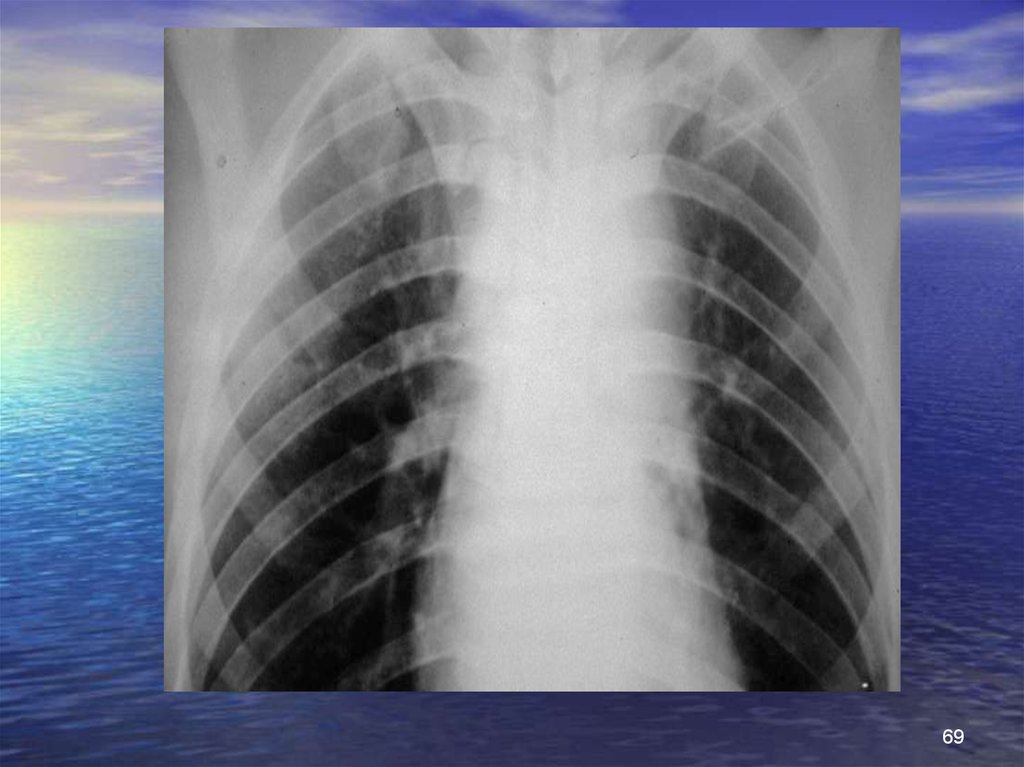

69.

69